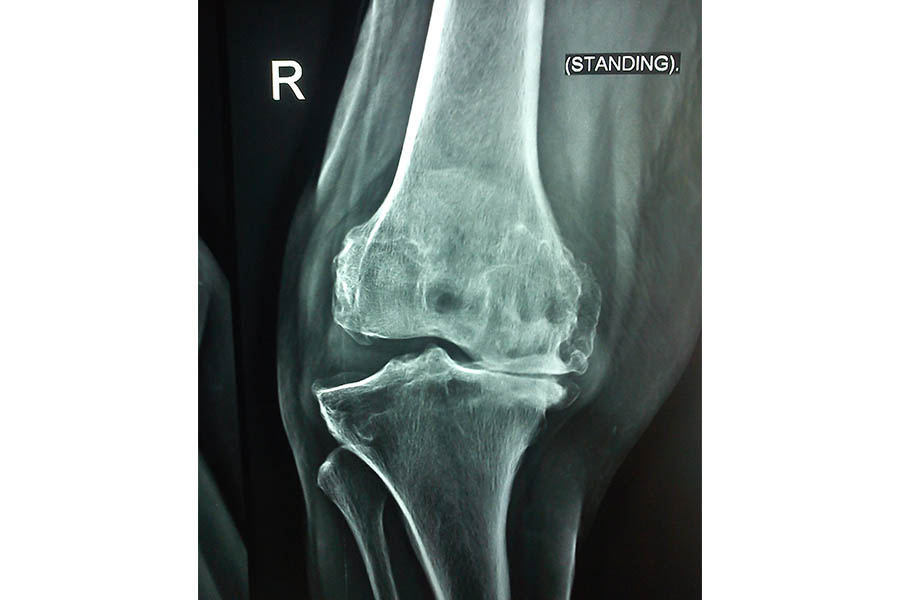

Total Knee Replacement

Case 1